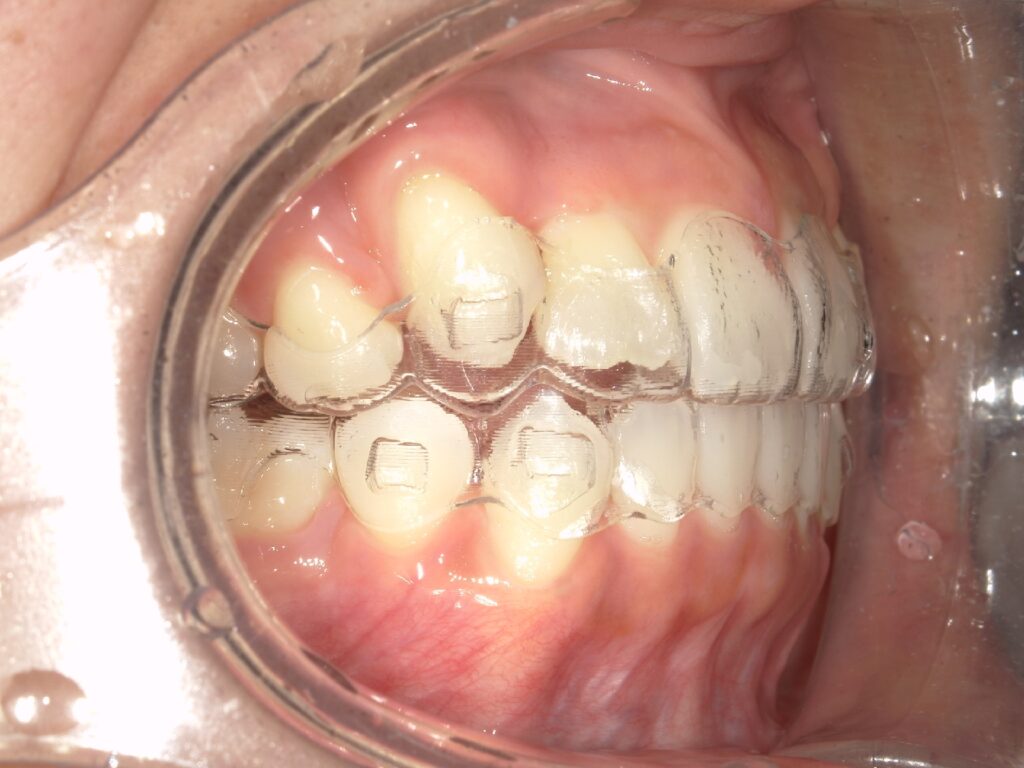

下記のケースでは、奥歯の噛み合わせが悪くなかったことから、患者様の希望もあり、部分矯正で対応いたしました。

上顎の前歯が大きく突出しています

明らかに前歯の突出感が改善し、患者様はこの時点でとても喜ばれていました

矯正治療終了時 部分矯正ということもあり、短期間で矯正治療を終了することができました